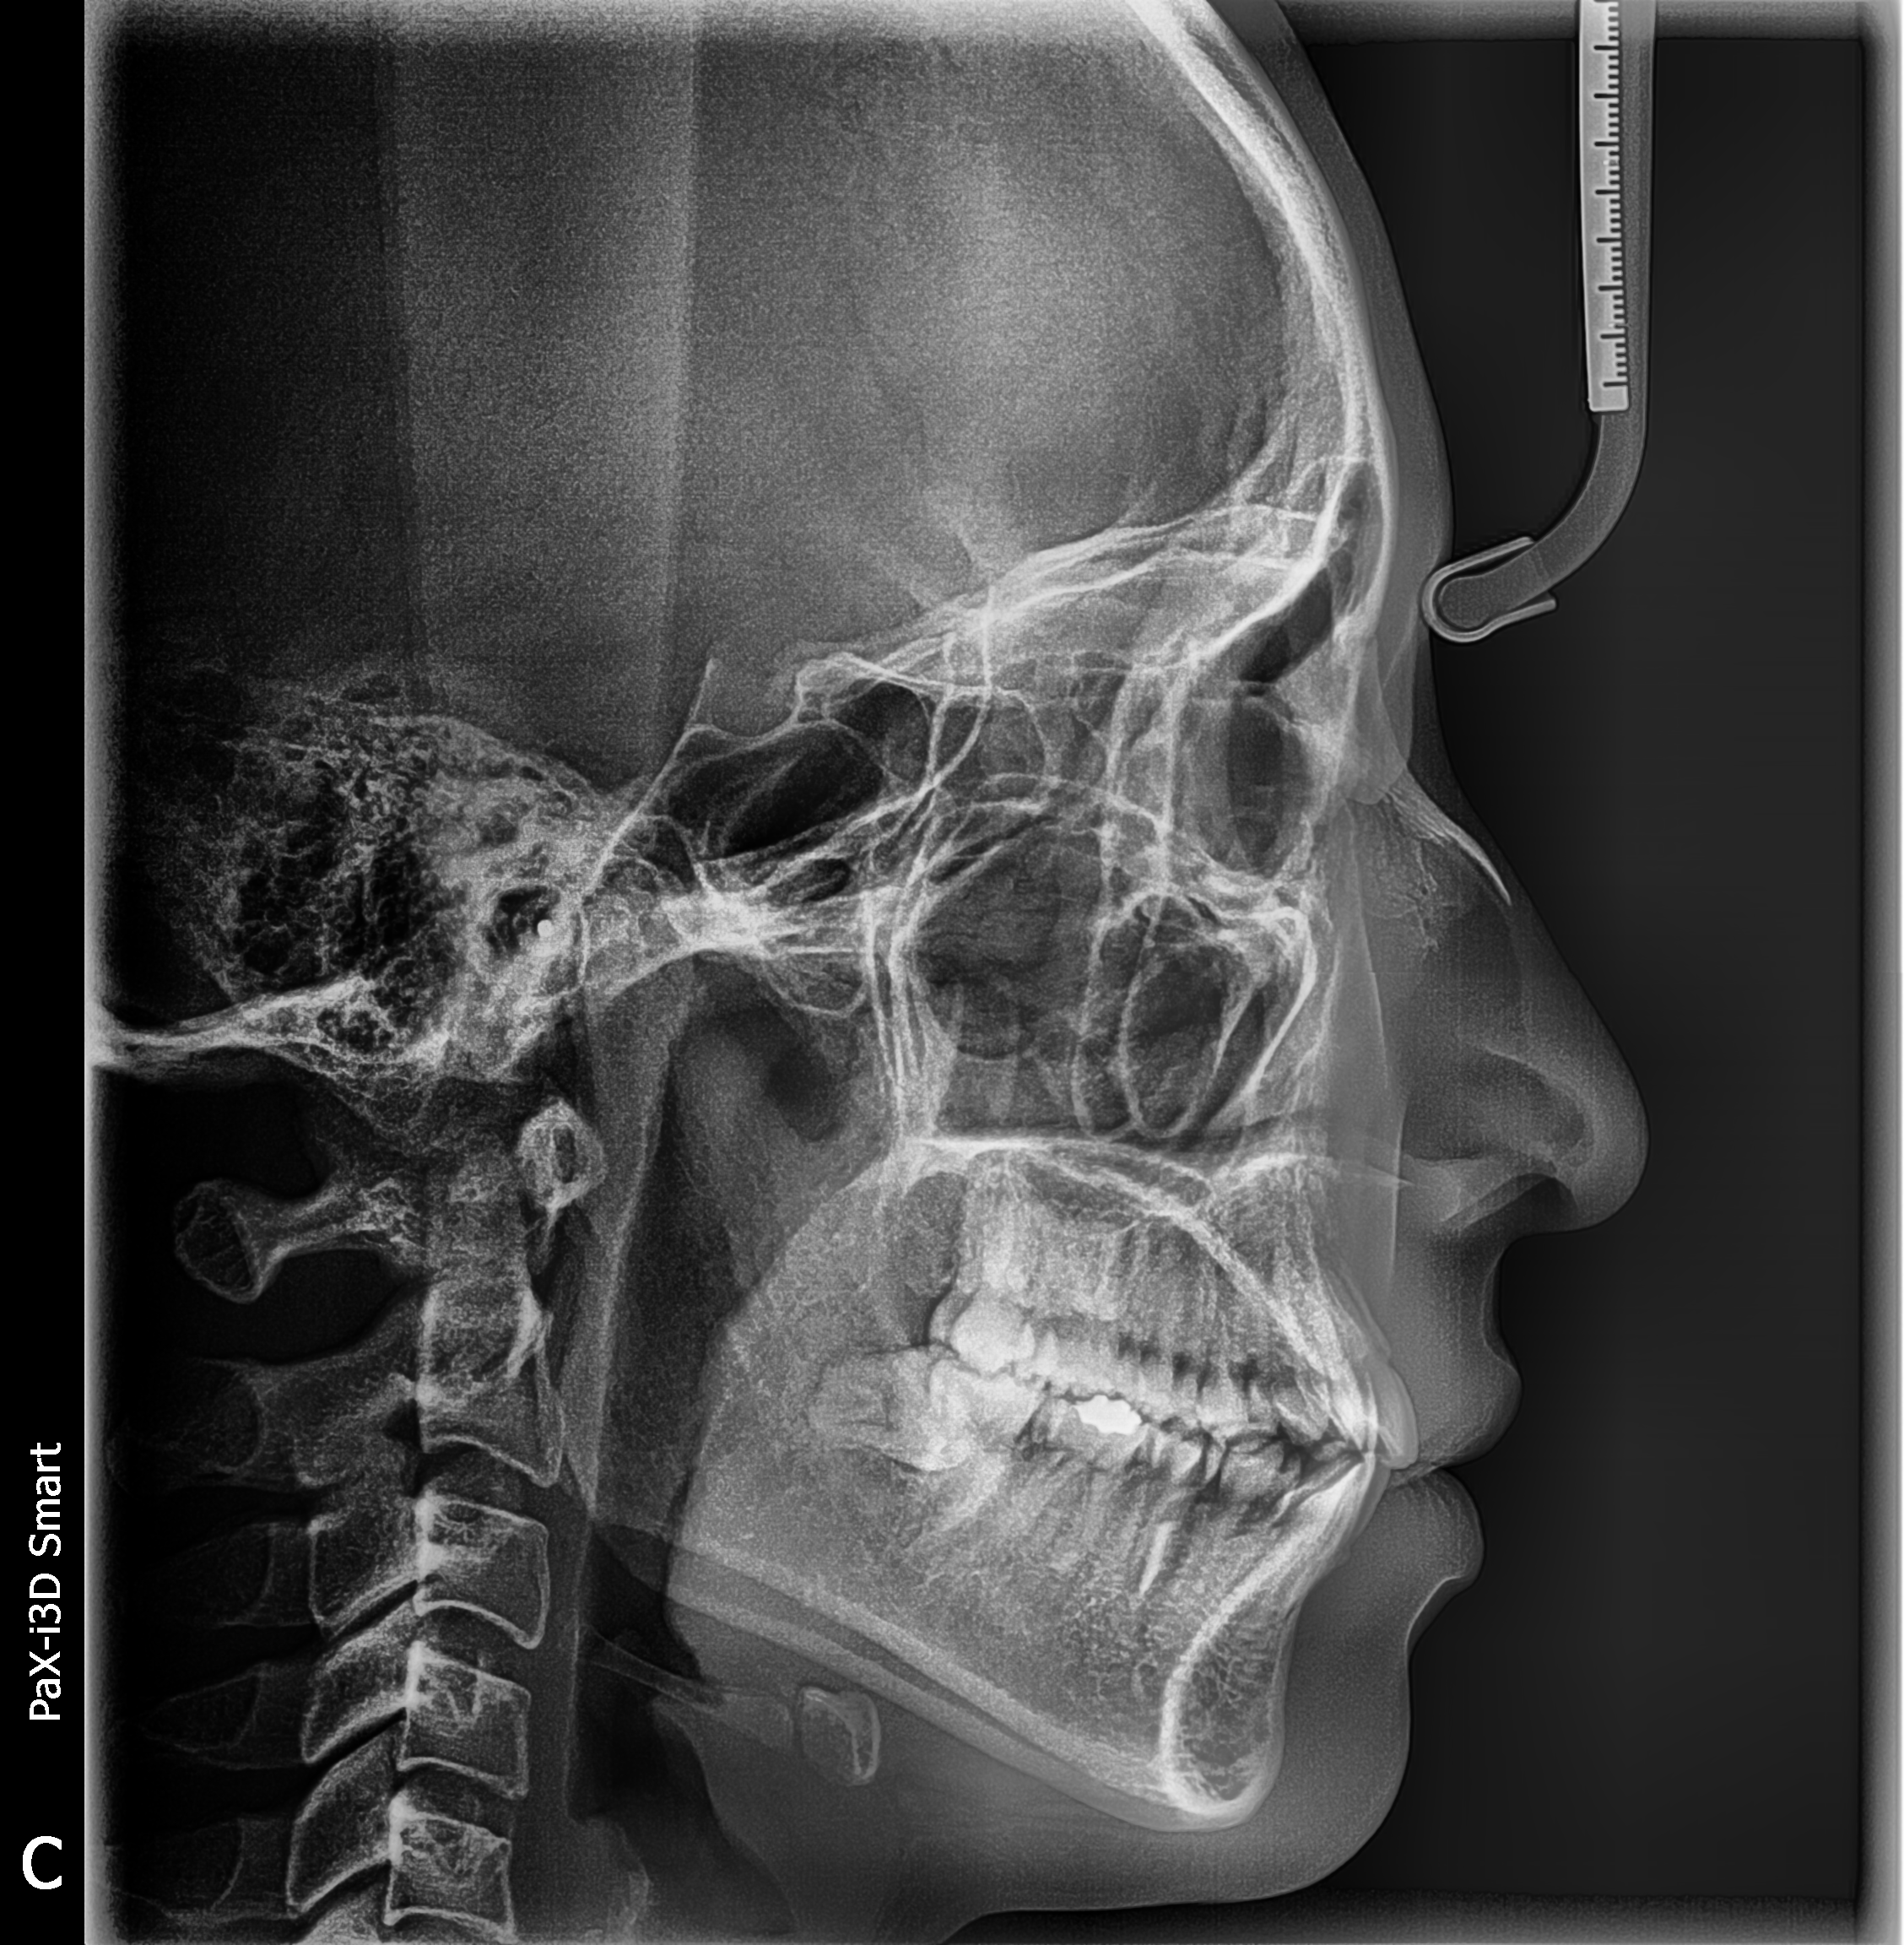

Technique de balayage du scanner

Taille d’image (21 x 23 cm) pour un diagnostic essentiel

Temps d’acquisition : 12.9 secondes

Qualité d’image en Haute Définition

Le Scan Ceph est un appareil de radiographie dentaire avancé, conçu pour fournir des images d'une précision exceptionnelle. Ce modèle propose des vues panoramiques, céphalométriques, et 3D, s'adaptant ainsi aux besoins variés de la pratique dentaire.